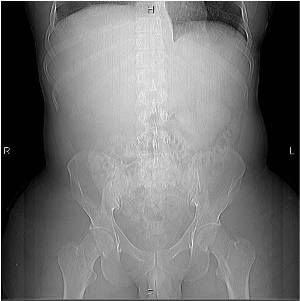

A 31-year-old male, recently on active duty in the military, presents to the ER with approximately one- week history of abdominal bloating, early satiety, and back pain. The patient has recently returned from overseas duty in Iraq, but otherwise has had no other significant travel history. On specific questioning, the patient reports he has “probably been exposed to toxic chemicals.” The patient is otherwise in healthy condition, and denies recent surgery, or illness, and takes no medication. He admits to social alcohol use only, and denies IV drug abuse.